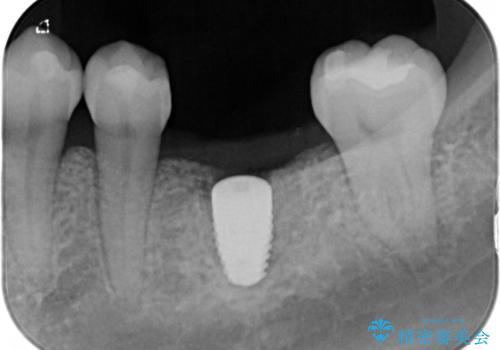

その過程で左下の6番目の歯は治療が必要な状態であることが分かり、被せ物を外して内部を確認してみると根が破折してしまっていることが判明しました。

歯が深い位置で破折している場合は基本的には抜歯が選択されます。

様々な治療プランを患者さんと相談させて頂き、最終的にインプラントで噛み合わせを回復させていくこととなり、まず悪くなっている歯を抜歯することから開始しました。